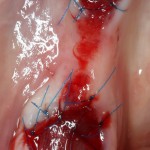

И вот тут я подумал, что пришла беда. Решил, что Mucograft Seal развалился (пациент курит), что с дня на день нужно ждать альвеолит.

Но оказалось иначе. Никаких беспокойств, никаких проблем, никакого дискомфорта. Сняли швы через неделю, с пациентом расстались на полтора месяца.

Клиническая картина в области удаленного зуба через полтора месяца: